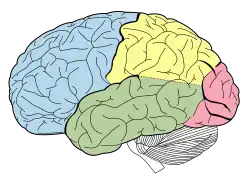

The frontal lobes are located at the front of each cerebral hemisphere and positioned anterior to the parietal lobes. It is separated from the parietal lobe by the primary motor cortex, which controls voluntary movements of specific body parts associated with the precentral gyrus.[10] The cortex here serves our ability to plan the day, organize work, type a letter, pay attention to details and control the movements of your arms and legs. It also contributed to your personality and behaviour.

The temporal lobes are a region of the cerebral cortex that is located beneath the Sylvian fissure on both the left and right hemispheres of the brain.[14] Lobes in this cortex are more closely associated with memory and in particular autobiographical memory.[15]

The parietal lobe is located directly behind the central sulcus, superior to the occipital lobe and posterior to the frontal lobe, visually at the top of the back of the head.[18] The make up of the parietal lobe is defined by four anatomical boundaries in the brain, providing a division of all the four lobes.[18]

The occipital lobe is the smallest of all four lobes in the human cerebral cortex and located in the rearmost part of the skull and considered to be part of the forebrain.[22] The occipital lobe sits directly above the cerebellum and is situated posterior to the Parieto-occipital sulcus, or parieto-occipital sulcus.[22] This lobe is known as the centre of the visual perception system, the main function of the occipital lobe is that of vision.